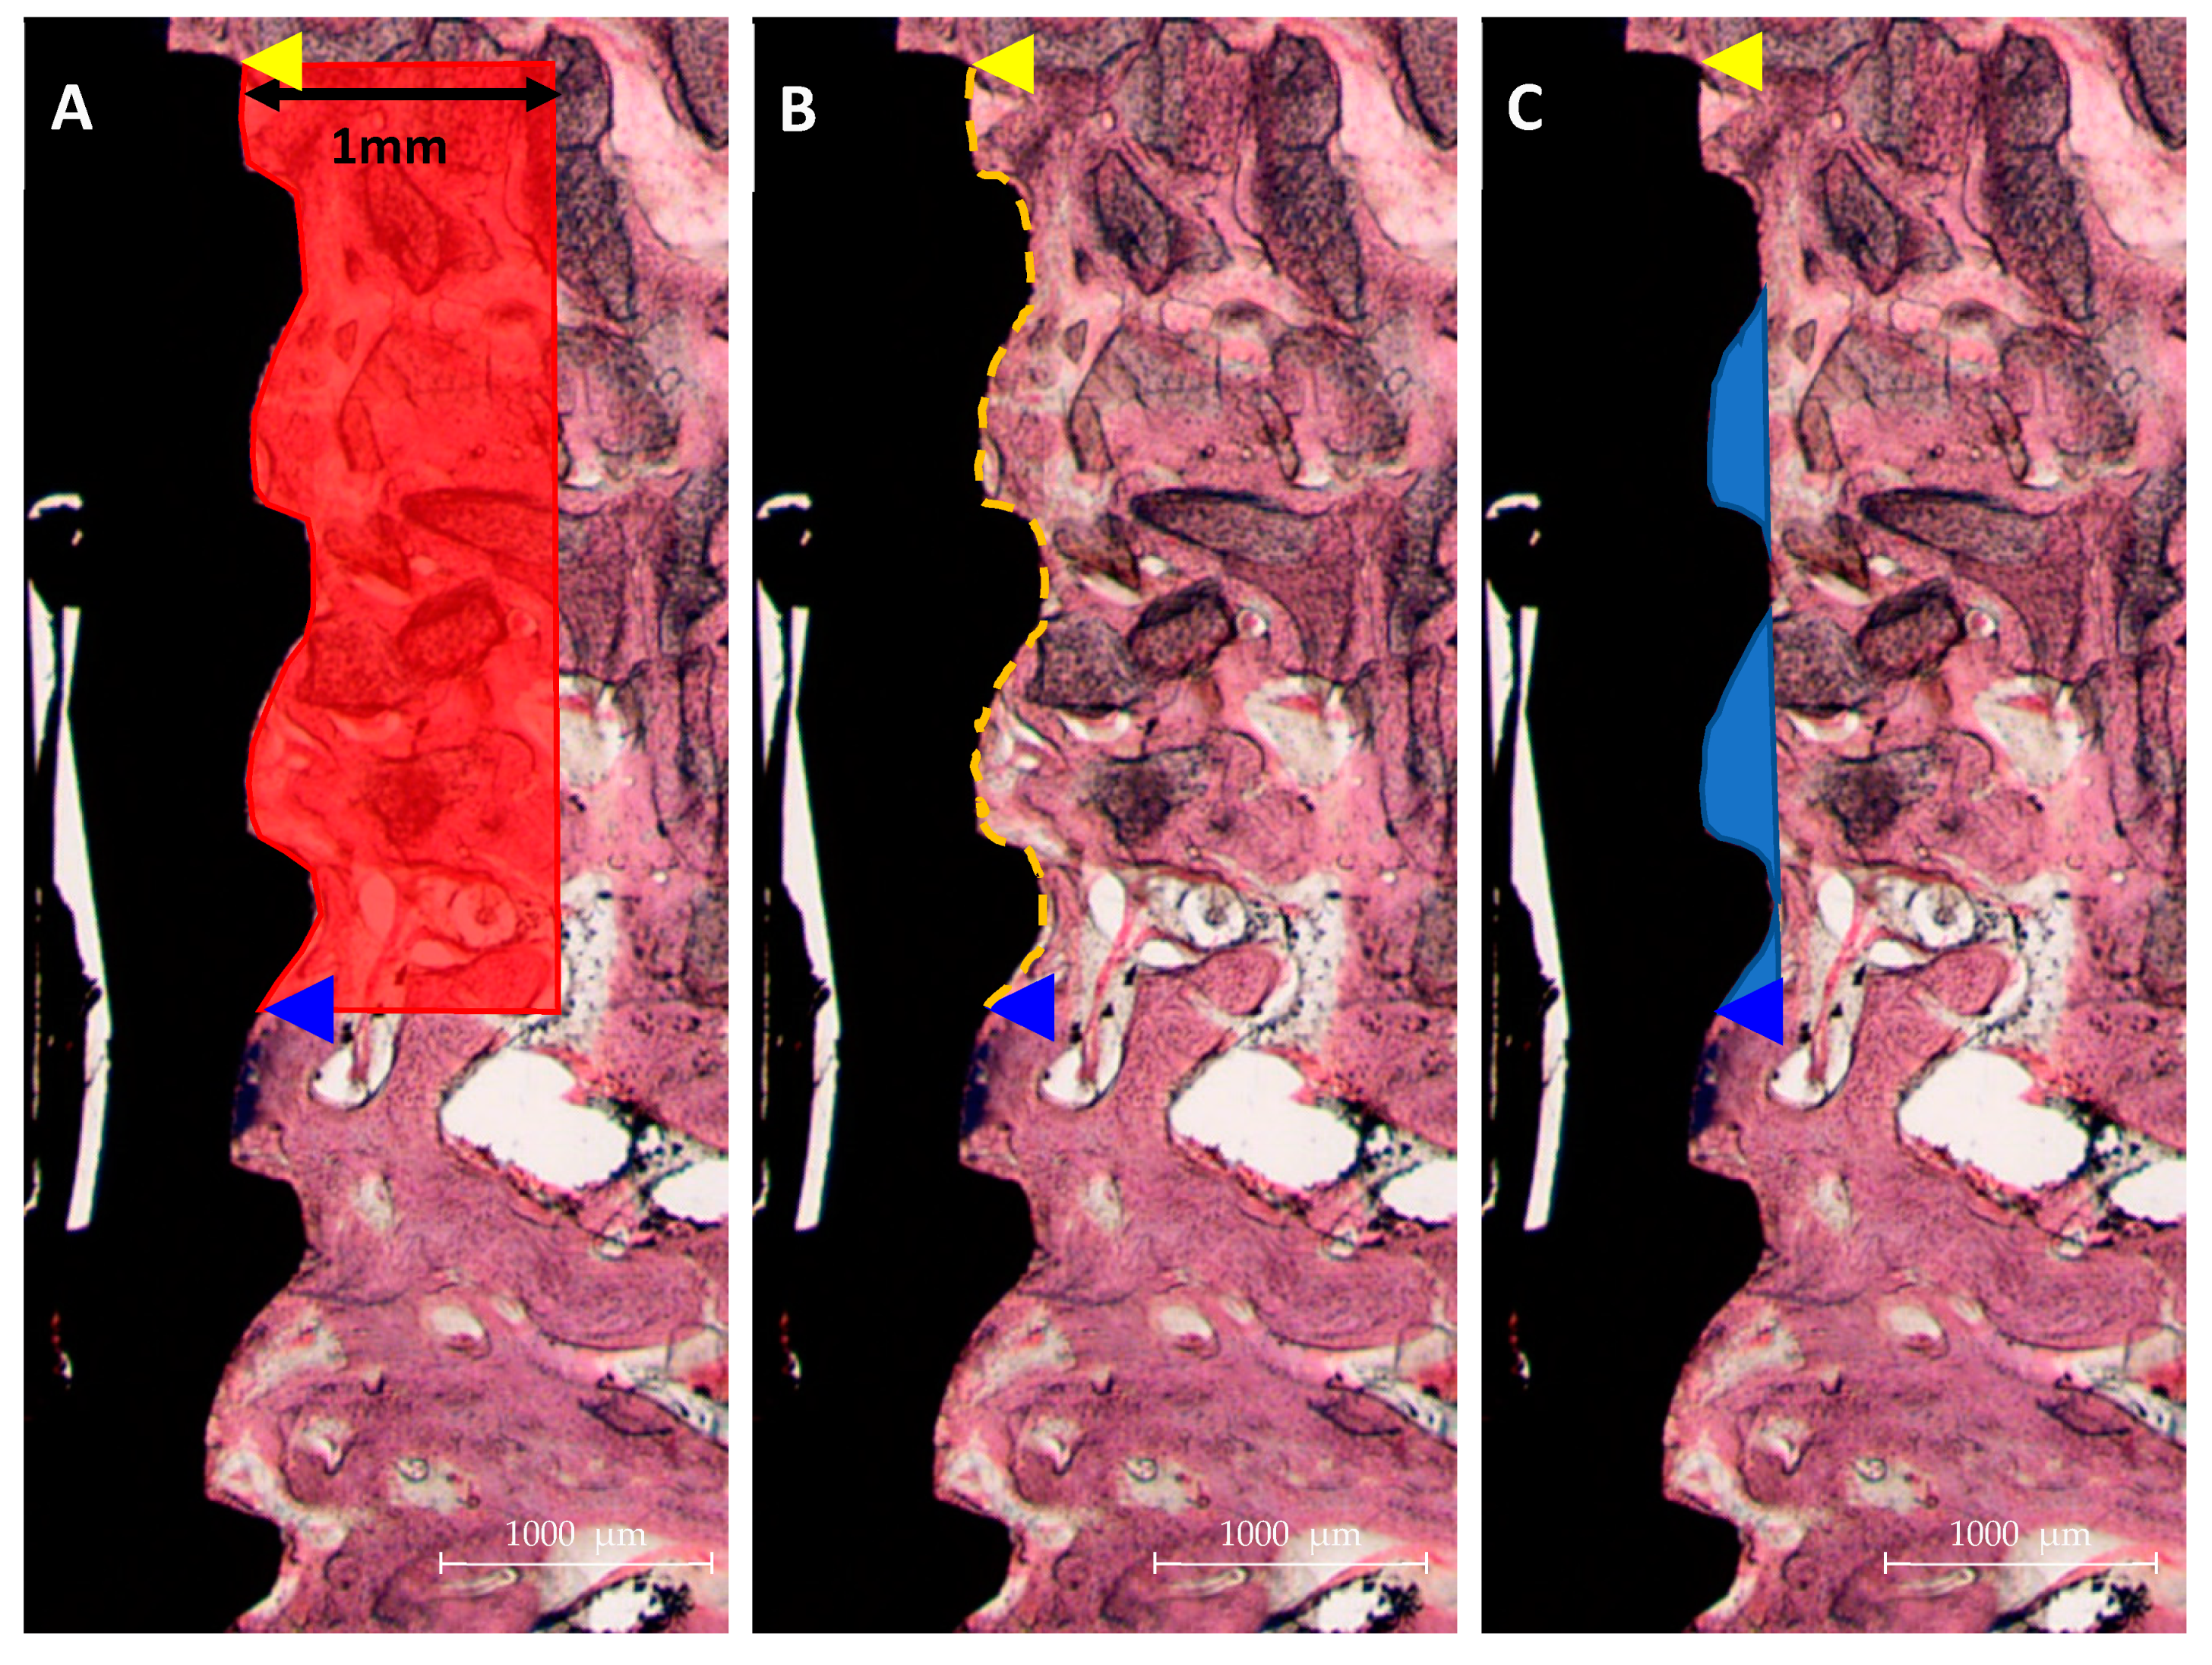

3.2.3. Histological Findings

3.2.4. Histometric Findings